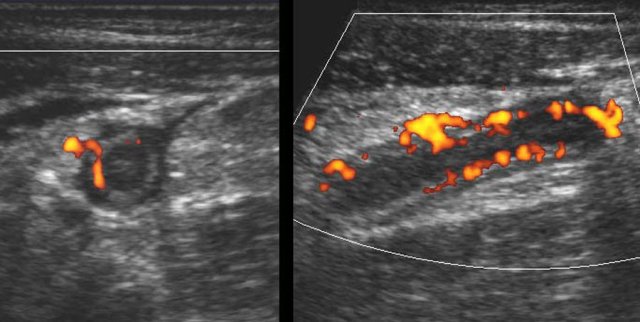

In this very lean patient with early acute appendicitis, US reveals dilatation of the distal appendix.

In plane A, Doppler US shows strong hypervascularization of the wall, however in plane B no vessels are visible in the appendix wall due to high intraluminal pressure.

Note the dilated, non-compressible, round appendix in B, bulging into the abdominal wall during compression (arrowheads), with only vascularization in the fatty meso-appendix.